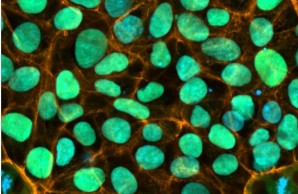

Central Project 1: Generation of human induced pluripotent stem cells

CP1 will establish human in vitro disease models to advance understanding of early-onset low BMD mechanisms